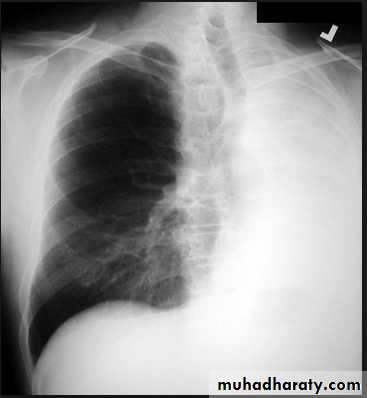

Lingular consolidation-PA. Patchy effacement of the left heart border.

Left upper lobe consolidation-Lat.

The opacification is sited anterior to the obliq- fissure-the position of the upper lobe.RLL collapse - PA.